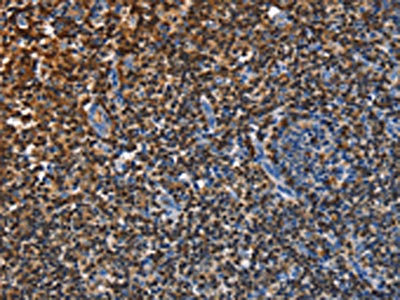

The image on the left is immunohistochemistry of paraffin-embedded Human tonsil tissue using CSB-PA598713(ENPP5 Antibody) at dilution 1/40, on the right is treated with fusion protein. (Original magnification: ×200)